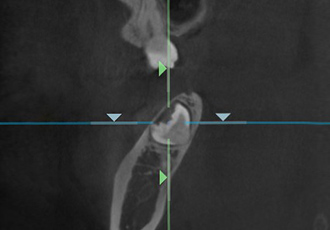

高精度な矯正治療には、治療技術だけでなく精密な検査や分析が必要不可欠です。当院では、歯の移動に関する口腔内の3次元情報を採取する歯科用CTや、事前にシミュレーションすることができる口腔内スキャナー(iTero)などといった専門的なデジタル設備を導入しております。

CT検査によって取得した口腔内の3Dデータから、歯の位置や埋伏歯(歯冠の全てまたは一部が埋まって出ていない歯)・過剰歯(決まった本数よりも多く生えている歯)などを確認します。

これらを事前に確認しておくことで、歯が移動する際に邪魔になってしまうのを防ぎます。また、歯の移動に大きく関係する骨の厚さなどの情報も得られ、精度の高い矯正治療のために不可欠な検査です。

CT検査を行うことで、さまざまな角度の断面から

歯の位置や方向を確認することができます。

アキシャル像

コロナル像

サジタル像

※症例に合わせて必要な場合にのみCT検査を行います。